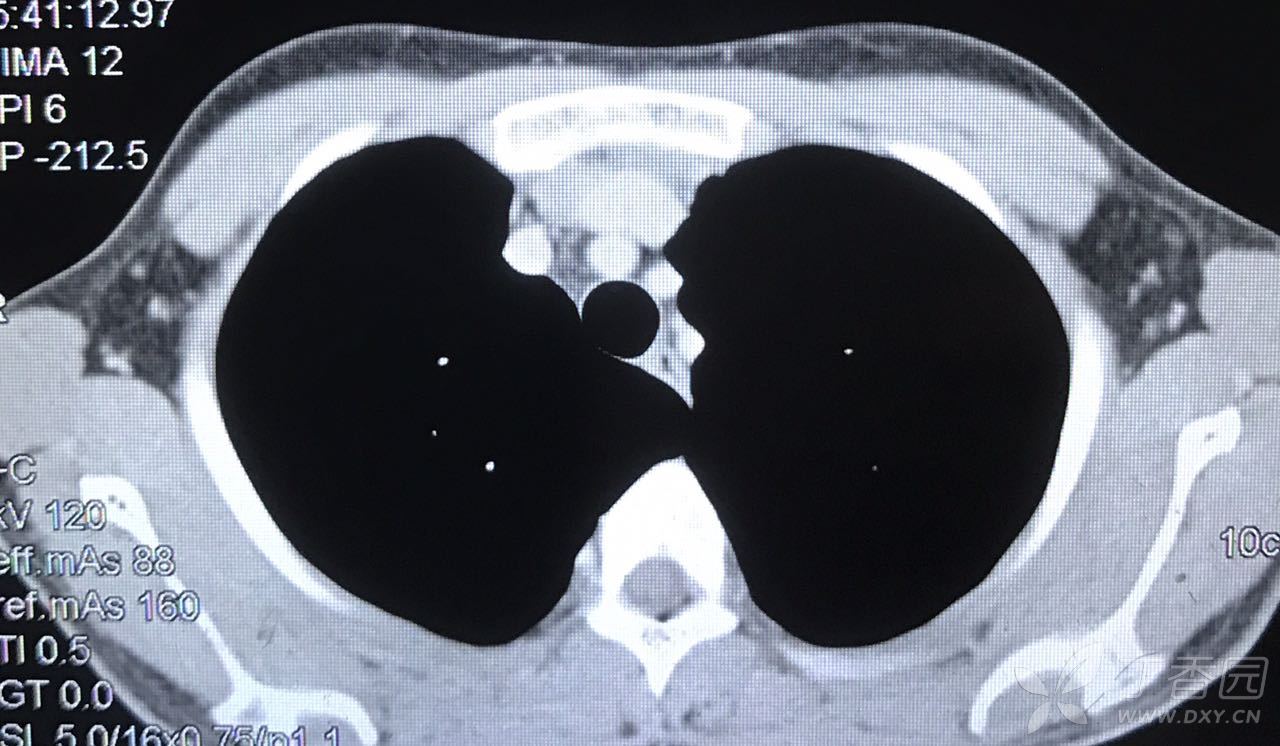

患者,中年男性,气紧半月.胸部ct如下,请各位老师帮忙看看

图片尺寸640x480